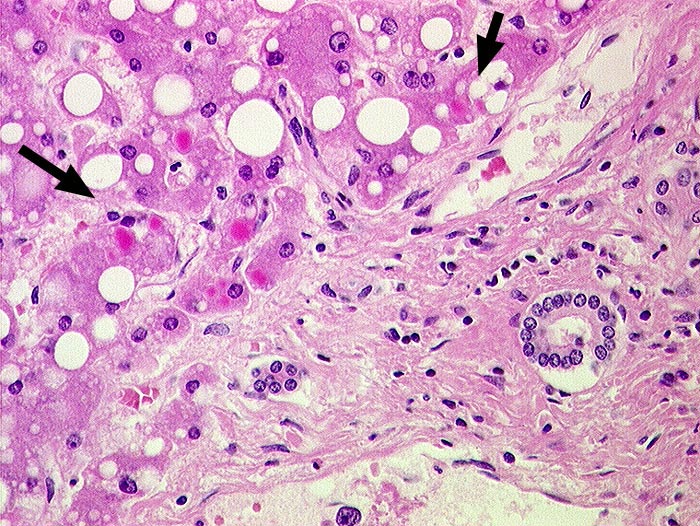

PathoPic ID 684 - alpha-1-Antitrypsinmangel

alpha-1-Antitrypsinmangel

Eosinophile Zytoplasmaeinschlüsse in periportalen Hepatozyten. Grobtropfige Verfettung.

alpha-1 Antitrypsin Typ Piz